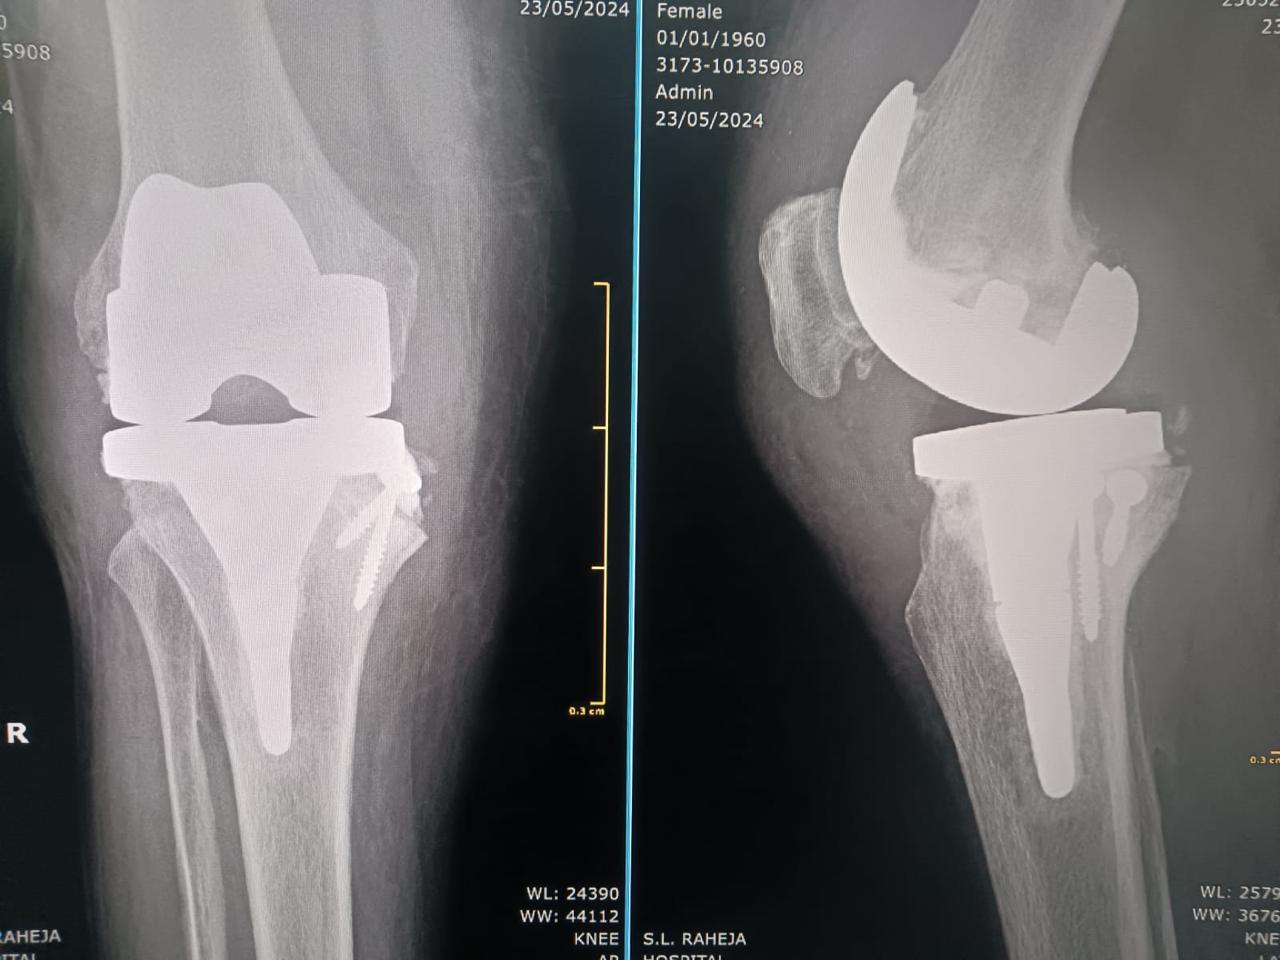

Total knee replacement, also called total knee arthroplasty, is a surgical procedure in which the worn out or damaged surfaces of the knee joint are removed and replaced with an artificial prosthesis.